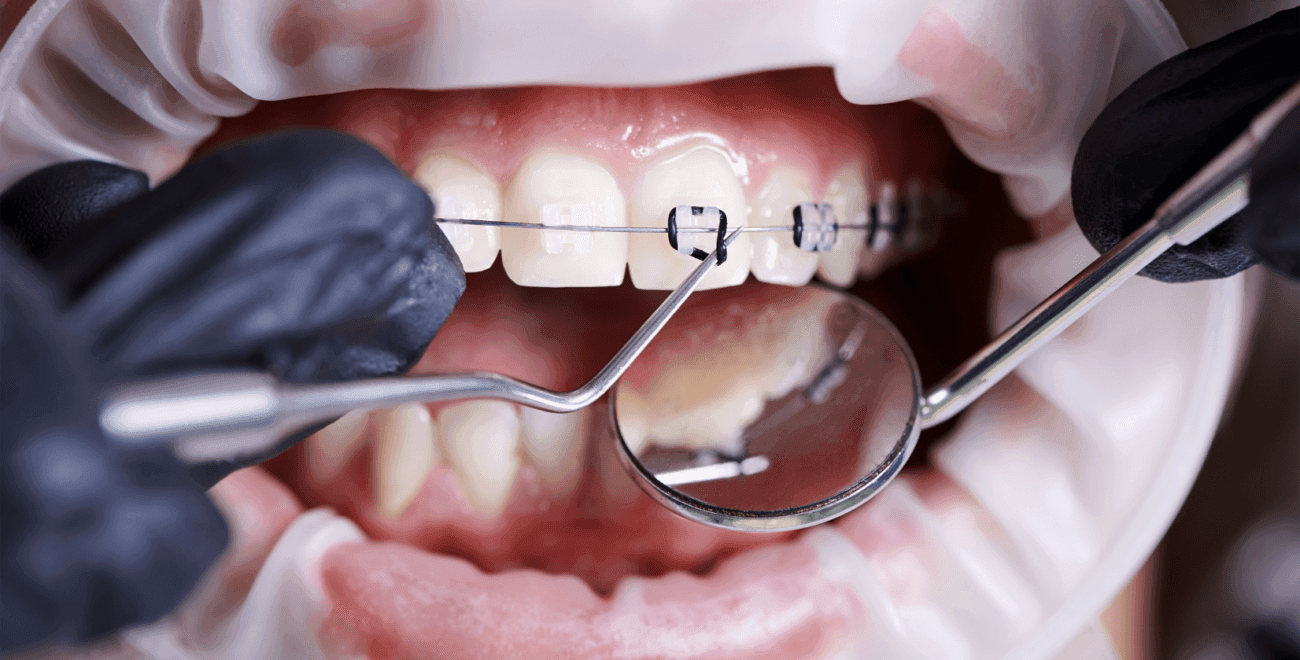

مراحل تركيب وتجربة تقويم الأسنان المعدني

يمر تركيب تقويم الاسنان المعدني بالعديد من المراحل وهي:

تركيب القوالب المعدني

تُركّب القوالب المعدنية من قبل الطبيب على أسنان المريض، وقد يتم الشعور بعدم الراحة ببداية العلاج، وسوف يقوم الطبيب في هذه المرحلة بمنح المريض نصائح لتنظيف أسنانه بشكل جيد.

المتابعة الدورية

يحتاج المريض في هذه المرحلة لزيارة طبيب الأسنان كل 4-6 أسابيع من أجل متابعة العلاج، كما أنه يُجري التعديلات اللازمة على التقويم لضمان أفضل النتائج.